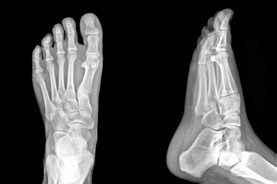

PAINFUL OR UNSIGHTLY BUNIONS?

At the Edmonton Foot Institute, our Doctors are trained to specifically treat problems associated with your feet or ankles. Below are several of the most common problems that we see on a day to day basis: